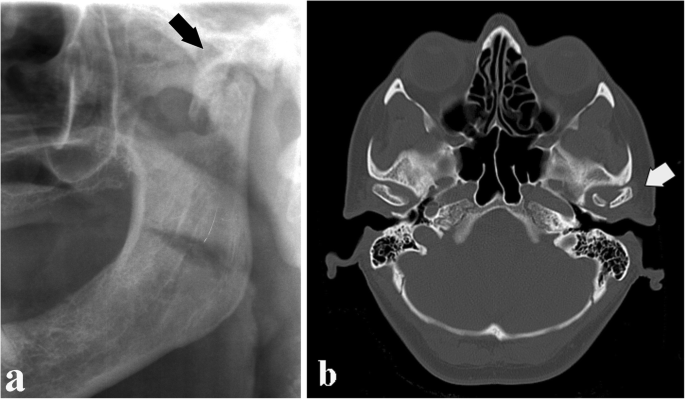

CT scan showing mandibular and facial bone fractures from trauma

Facial trauma refers to injuries affecting the face, jaws, teeth, and facial bones, often caused by road accidents, falls, sports injuries, workplace accidents, or assaults. These injuries may involve fractured jaw bones, broken facial bones, damaged teeth, cuts, swelling, or difficulty in opening the mouth.